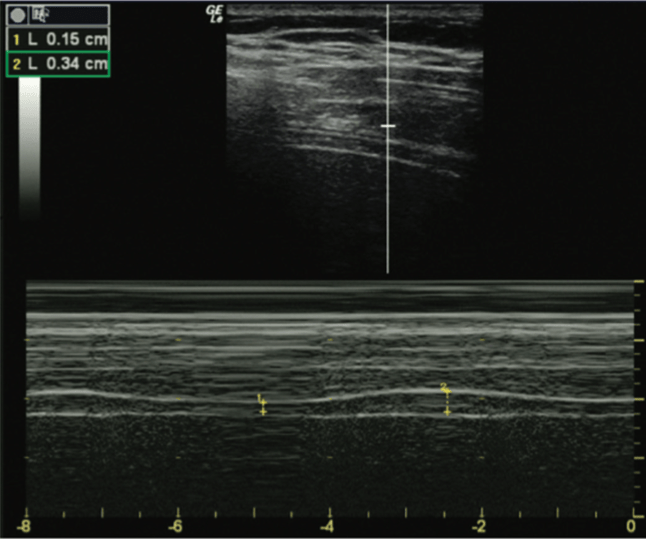

For DTF measurement, a high-frequency transducer is used in the same position as DE measurement, and M-mode is also employed. The diaphragm thickness is less during expiration (DTe) and greater than inspiration (DTi). The DTF is calculated as (DTi – DTe)/DTe.

A diaphragmatic thickening fraction <30% (with a range of 24%–35% in most studies) is considered abnormal. The figure below shows normal diaphragmatic thickening fraction using M-mode.

Our patient had a DTF of 4.4% and DE of 2.7 mm, so there is clear diaphragmatic dysfunction.

Learning Point: A DE value of ≤10-15 mm for normal spontaneous breathing and <25 mm for maximal inspiratory effort, or DTF < 30%, is associated with diaphragmatic dysfunction.